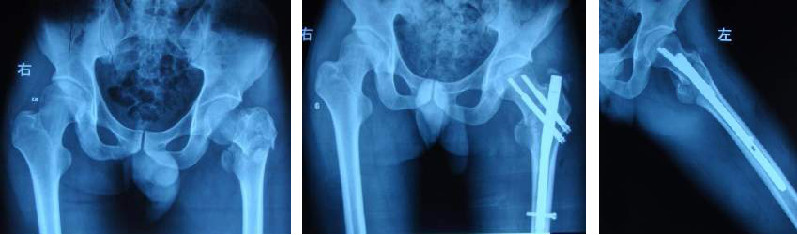

Стабильность внутренней фиксации переломов обычно зависит от пяти факторов: качества кости, типа перелома, репозиции, выбора внутренней фиксации и положения внутренней фиксации по отношению к кости.Репозиция перелома важна для стабильности после внутренней фиксации и должна быть направлена на достижение либо анатомической репозиции, либо стабильной неанатомической репозиции.Таким образом, целью репозиции является достижение стабильности перелома.Способ репозиции может быть закрытым или инцизионным.Независимо от сложности типа перелома сначала следует попробовать закрытую репозицию.

Винт обладает сильным эффектом фиксации в головке бедренной кости, даже в случае остеопороза.

Механизм скольжения во втулке предотвращает проникновение конца гвоздя в головку бедренной кости или вертлужную впадину и непосредственную передачу отрицательной гравитации на кость.

Механизм силового скольжения удерживает перелом на месте и уменьшает несращение.

Он имеет двойную функцию сжатия и скольжения с динамическим и статическим эффектом сжатия.

DCS и режущие пластины под углом 95 градусов для антикротальных переломов:

Он может правильно выбрать точку входа винта в соответствии с конкретной ситуацией перелома, и операция удобна.

Силовой компрессионно-натяжной винт находится под прямым углом к пластине, что отвечает биомеханическим требованиям бедра.Во время нагрузки отрицательная сила сначала прикладывается к короткому плечу пластины, а затем распределяется по каждому винту, так что напряжение рассеивается и фиксация получается исключительно прочной.

Немного большее количество винтов DCS в области перелома повышает прочность, а область перелома можно перекрыть и зафиксировать, что снижает частоту послеоперационных осложнений.